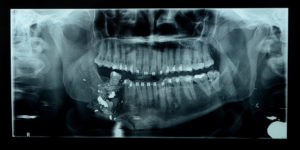

Inédita, a cirurgia consistiu em transplantar retalho microcirúrgico da fíbula do paciente – osso da perna, antigo perônio, ao lado da tíbia (canela), pela parte externa. O paciente, servidor público da área de segurança pública, foi vítima de ferimento na face por arma de fogo, afetando diretamente a mandíbula direita, no dia 22 de abril.

O cirurgião bucomaxilofacial Francisco Amadis destacou que a cirurgia reconstruiu parte do osso da mandíbula. “Boa parte da mandíbula direita foi destruída pelo projétil. Trabalhamos em parceria com cirurgião plástico, especialista em microcirurgia. Enquanto uma equipe preparou o local para receber o retalho microvascular na mandíbula, a segunda equipe retirou o retalho da fíbula, da perna do paciente, para a reconstrução”, explicou Amadis.

Segundo o médico, a cirurgia foi realizada no momento ideal e o paciente irá recuperar a qualidade de vida. “Após mais de 30 dias do acidente, com todos os exames e procedimentos pré-operatórios realizados, reconstruímos a mandíbula, devolvendo qualidade de vida ao paciente”, disse Amadis.

“Com esta cirurgia, iremos devolver ao paciente a função mastigativa e de fonação, e articulação dos sons. Além de também devolver a deglutição”, informou Amadis. “O mais importante é o retorno do paciente ao convívio social e às suas atividades laborais”, complementou o médico.